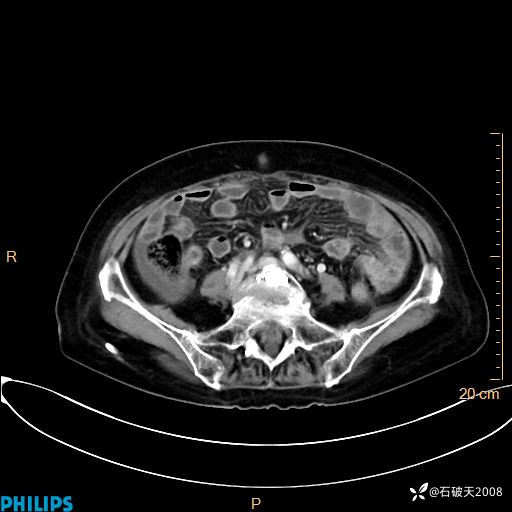

动脉期